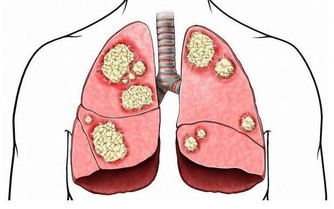

4、胸悶、胸痛

胸悶、胸痛是血栓來臨最常見的症狀之一。因為血栓初期,血管中非常容易出現凝結而成的血栓,如果其掉落並隨血液流入肺部,可能引發胸悶胸痛症狀。

一旦形成肺栓塞,隨著呼吸疼痛會逐漸加重,且一般是刺痛或銳痛。因此,如果身體出現胸悶胸痛一定要特別警惕,尤其是老年人。